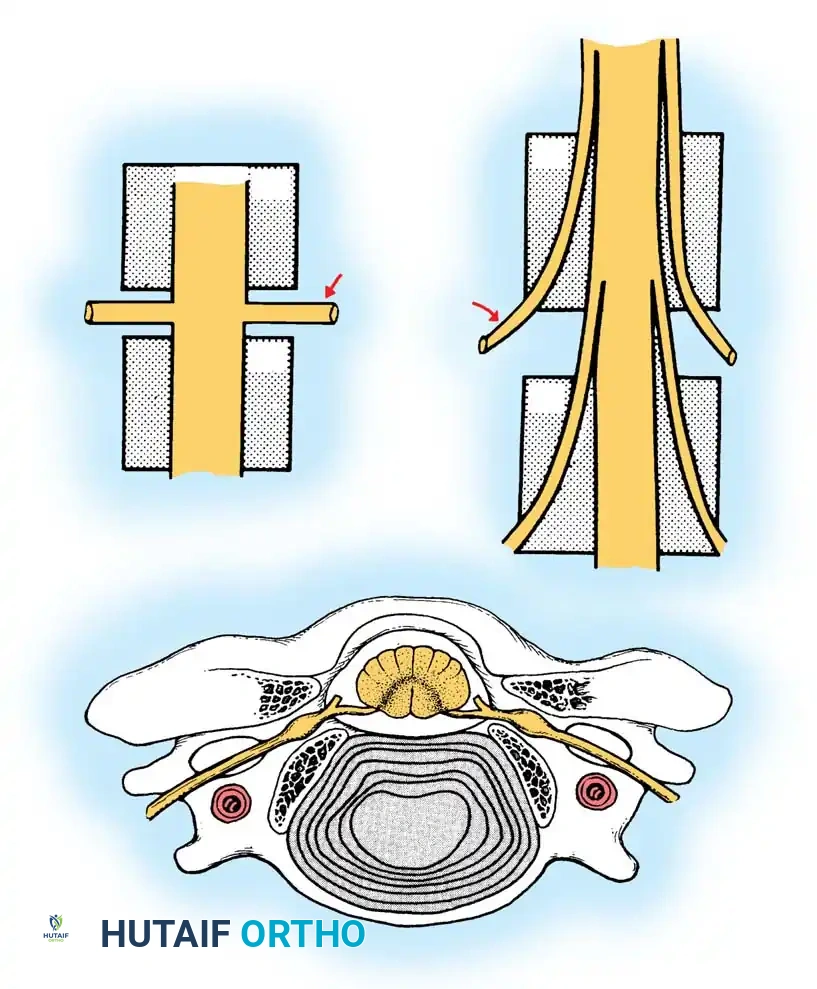

Uncovertebral Joint Hypertrophy

In stark contrast to the lumbar spine, hypertrophic changes in the cervical spine predominantly affect the uncovertebral joints (joints of Luschka or uncinate processes).

The uncinate process forms the ventral wall of the intervertebral foramen. As hypertrophic osteophytes develop around the uncovertebral joints, facet joints, and vertebral bodies, they encroach upon the neuroforamen, leading to lateral root pressure. In end-stage disease, progressive stiffening of the cervical spine and global loss of motion are the usual results. Occasionally, massive anterior hypertrophic spurring can mechanically compress the esophagus, resulting in dysphagia.